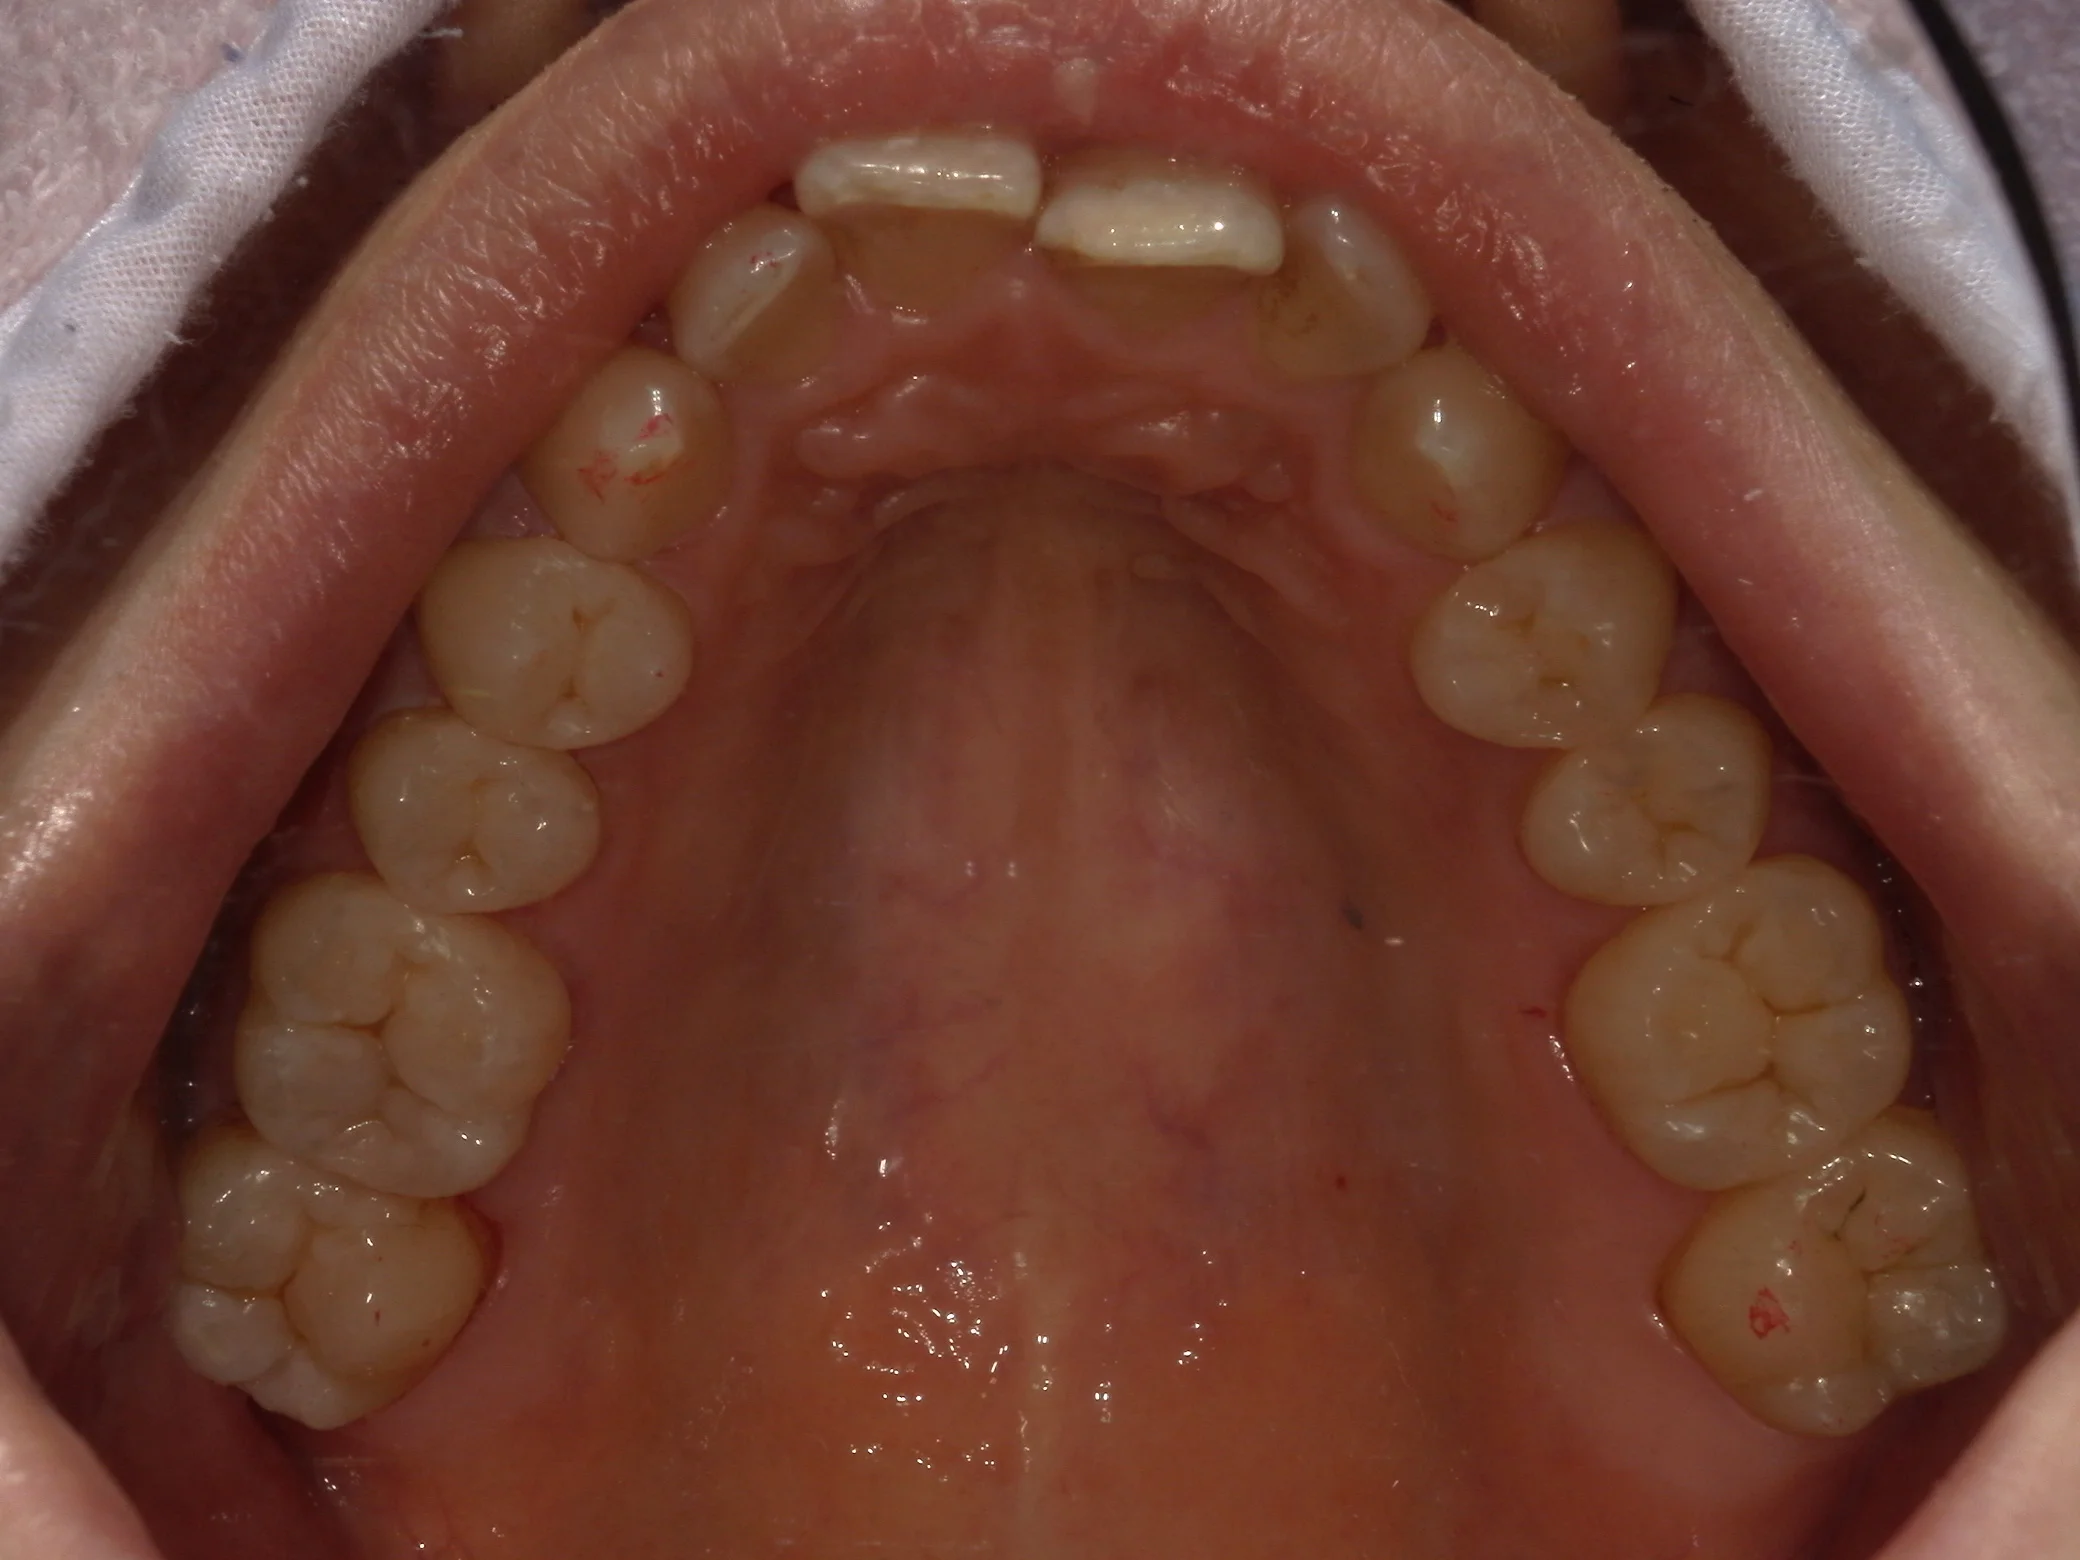

全体が写る写真は術前がこちらで

術後がこちらになります。

金属が一つも無くなり、綺麗に仕上がったかと思います!

なるべく長く使って貰えると嬉しいですね!